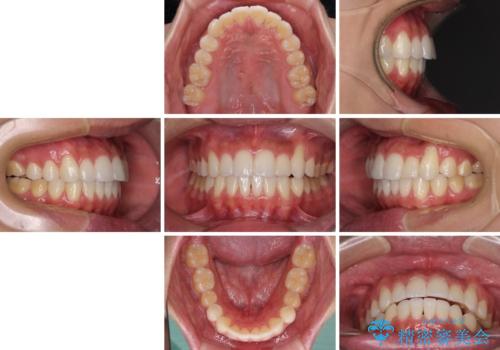

八重歯と奥歯のクロスバイト 上顎骨を拡大してインビザラインで矯正

上顎骨を思い通りに拡大できたため、当初の計画通りに非抜歯矯正で仕上げることができました。